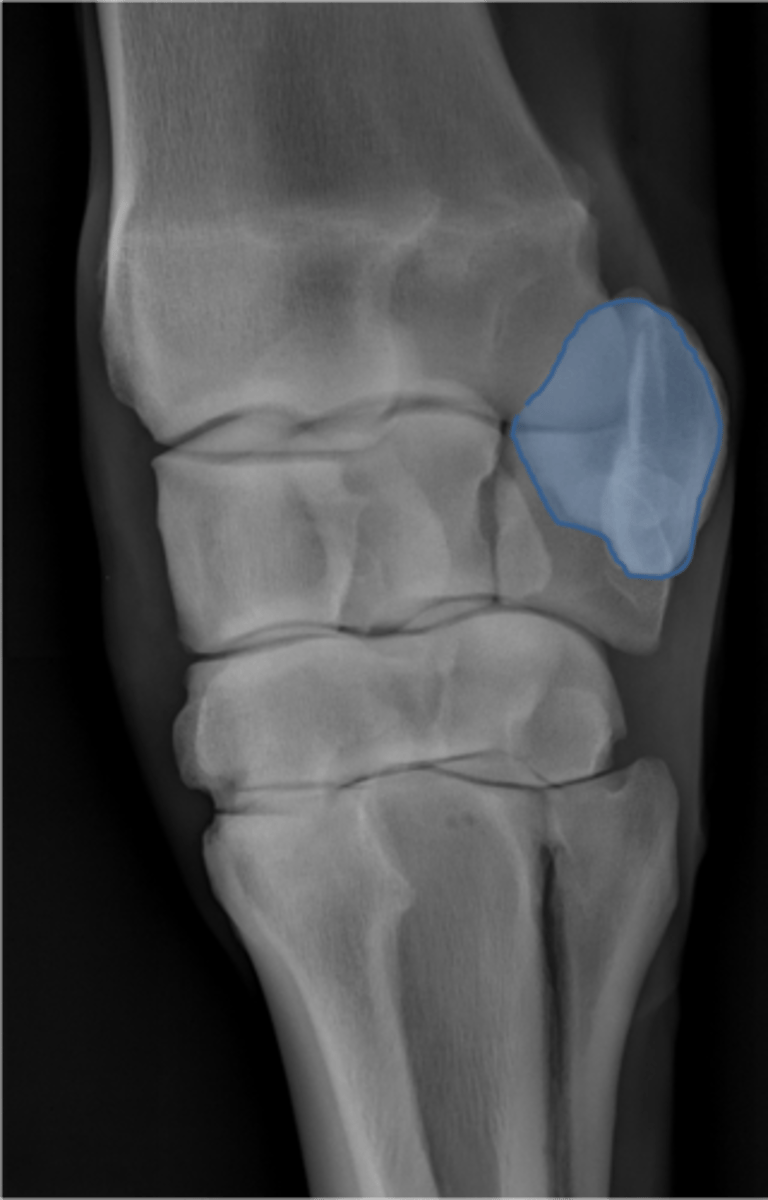

Proximal sesamoid bone

Sagittal ridge

Condyles of third metacarpal bone

Palmar process of P2

Proximal sesamoid bones

Sagittal ridge

Attachment of collateral ligaments

Proximal sesamoid bones

Palmar process of P1

Condyles of the third metacarpal bone